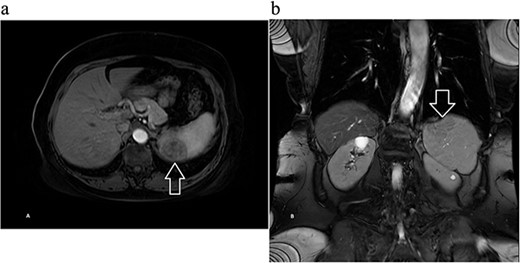

A 68-year-old female with a history of hypertension, gastroesophageal reflux disease, and hyperlipidemia was referred to the general surgery clinic for evaluation of a splenic mass found incidentally on a computed tomography (CT) scan performed in the emergency department, after a tree branch fell and injured her left flank. The patient was complaining from left flank pain at the time of presentation, and her physical exam showed a small nontender bruise on her left flank. Laboratory results were within normal range. CT of the abdomen and pelvis with intravenous (IV) contrast revealed an indeterminate round 3.5-cm hypoattenuating lesion in the spleen (Fig. 1).

Computed tomography of the abdomen and pelvis with contrast showing an indeterminate round 3.5 cm hypo-attenuating lesion in the spleen: (a) axial and (b) coronal views with arrow marking the mass.